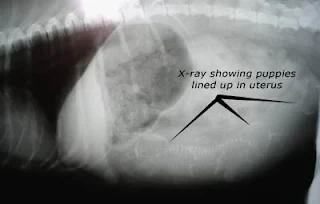

| Ảnh X-quang xác định số con trên chó. |